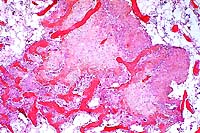

4x

obj

10x

40x

- Case 20-3. Tumor. Normal bone is replaced by streams

& bundles of spindle cells and multifocal clusters of multinucleate

giant cells.

20x

- Case 20-4. Cervical vertebra. Multifocally areas of

endochondral bone partly replaced by granular mineralized debris

are surounded by macrophages, foreign body giant cells, and fibrous

connective tissue.